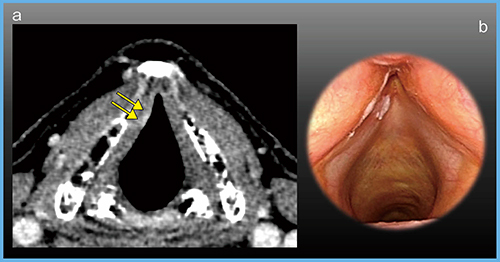

症例2の声門がんは5mm大の小さな表在がんであるが,Aquilion Precisionで描出が可能であった(図6)。表在性低容積病変は,従来CTでは指摘困難なことがあり,内視鏡的所見で診断されることが多かったが,Aquilion Precisionでは,深さ1mm程度の表在がんも描出可能になった。

図6 症例2:声門がん(T1a)

a:超高精細CT(1mm厚,AIDR 3D) b:内視鏡画像